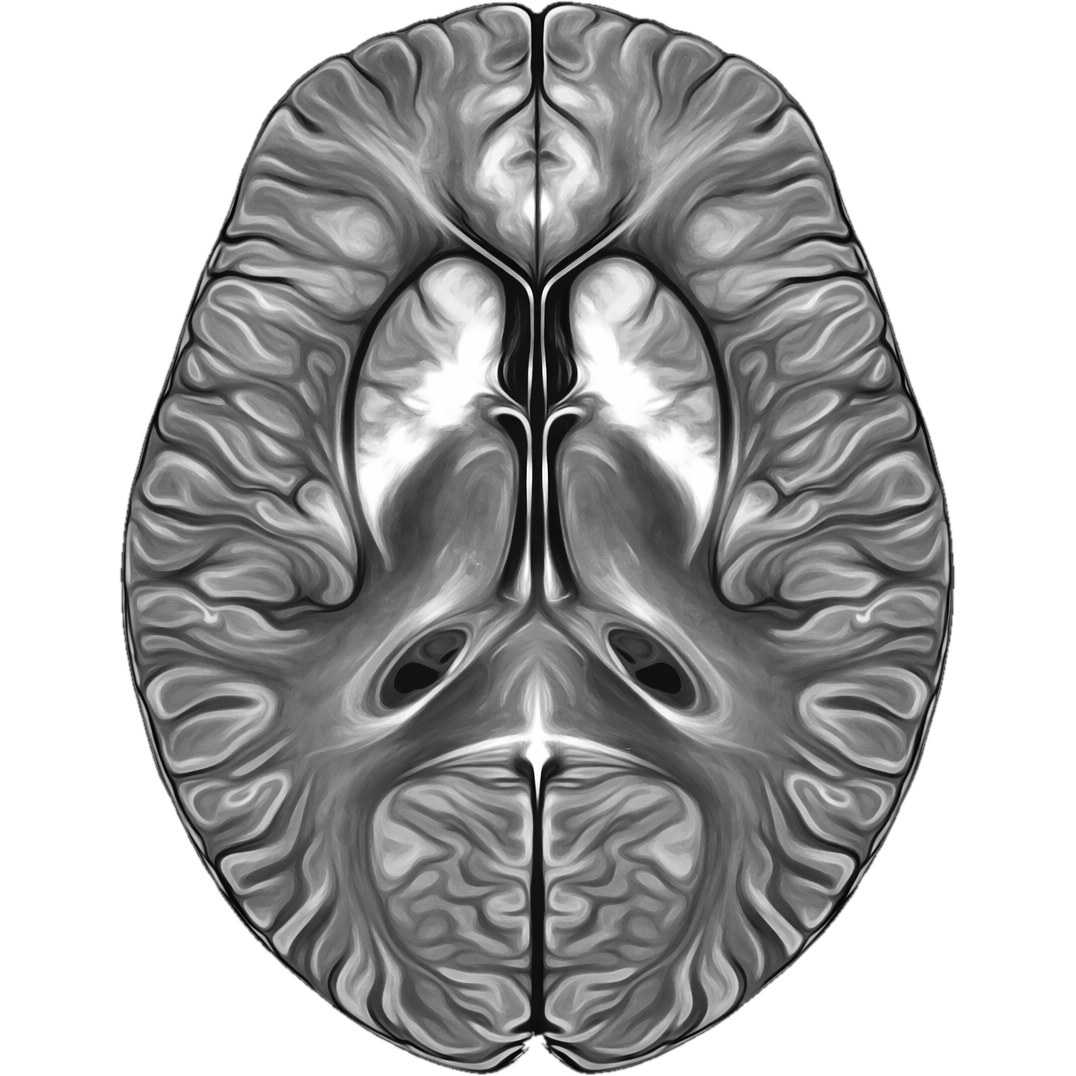

Quantitative Susceptibility Mapping in the browser

QSMbly is a browser-based application for Quantitative Susceptibility Mapping (QSM). It runs entirely in your web browser using WebAssembly, providing near-native performance without requiring any software installation or data upload.